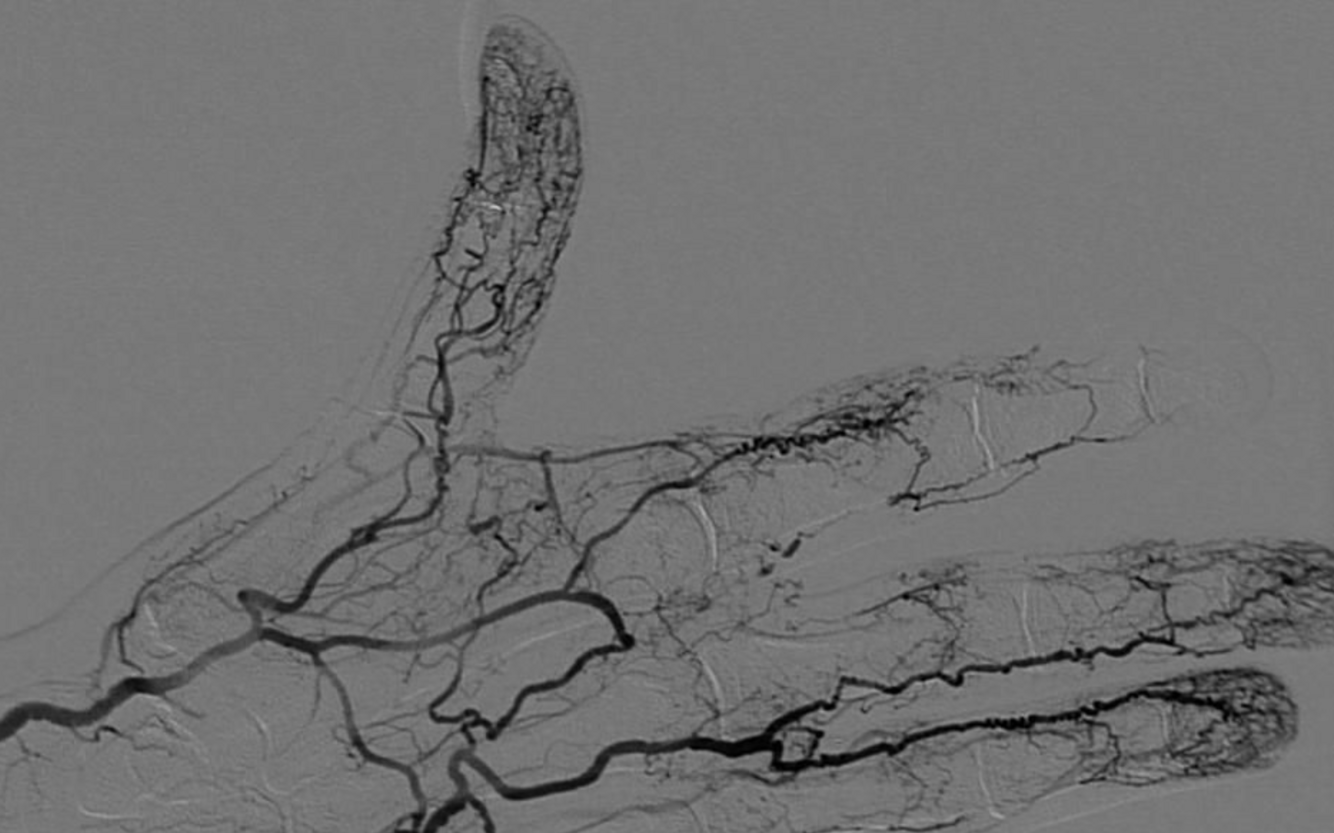

A

Angiography, which shows segmental occlusions and corkscrew collaterals.

What findings on angiography suggest Buerger’s disease?

Corkscrew collaterals and segmental occlusions of small- and medium-sized arteries.